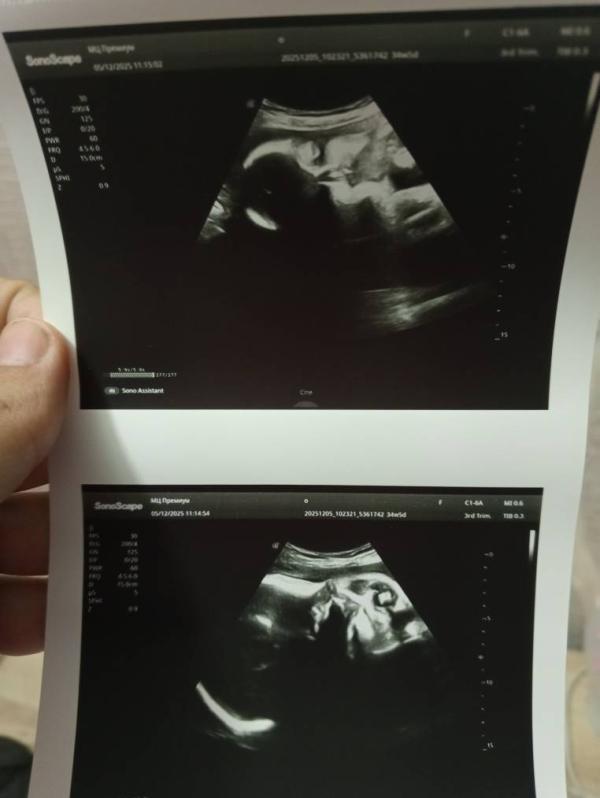

Сегодня ровно 35 недель

По узи всё отлично 🙏🏻

Малышка весит 2,610г

Ровно в 30 недель весила 1,650г

Фото сделать не получилось, она закрыла лицо пуповиной и руками

Радует, что она перевернулась головкой вниз, надеюсь так и останется до родов 🤞